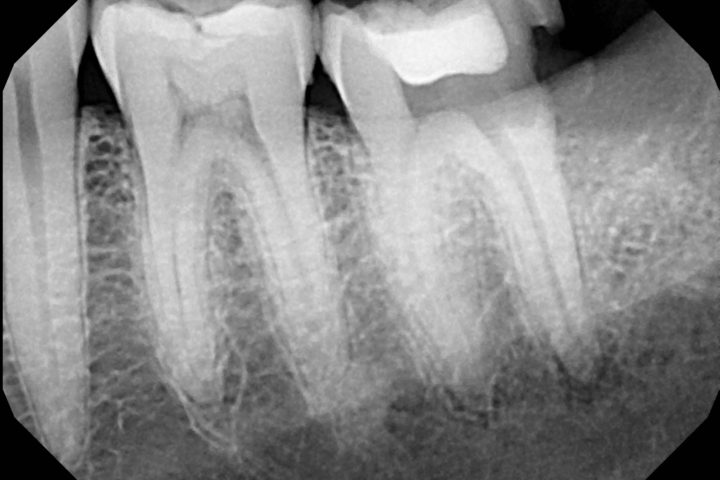

Diagnosi con TAC Cone Beam

Grazie alla tecnologia Cone Beam 3D, l’estrazione dei denti del giudizio e delle radici dentali fratturate viene pianificata con la massima precisione, valutando posizione, profondità e rapporti con le strutture anatomiche vicine.